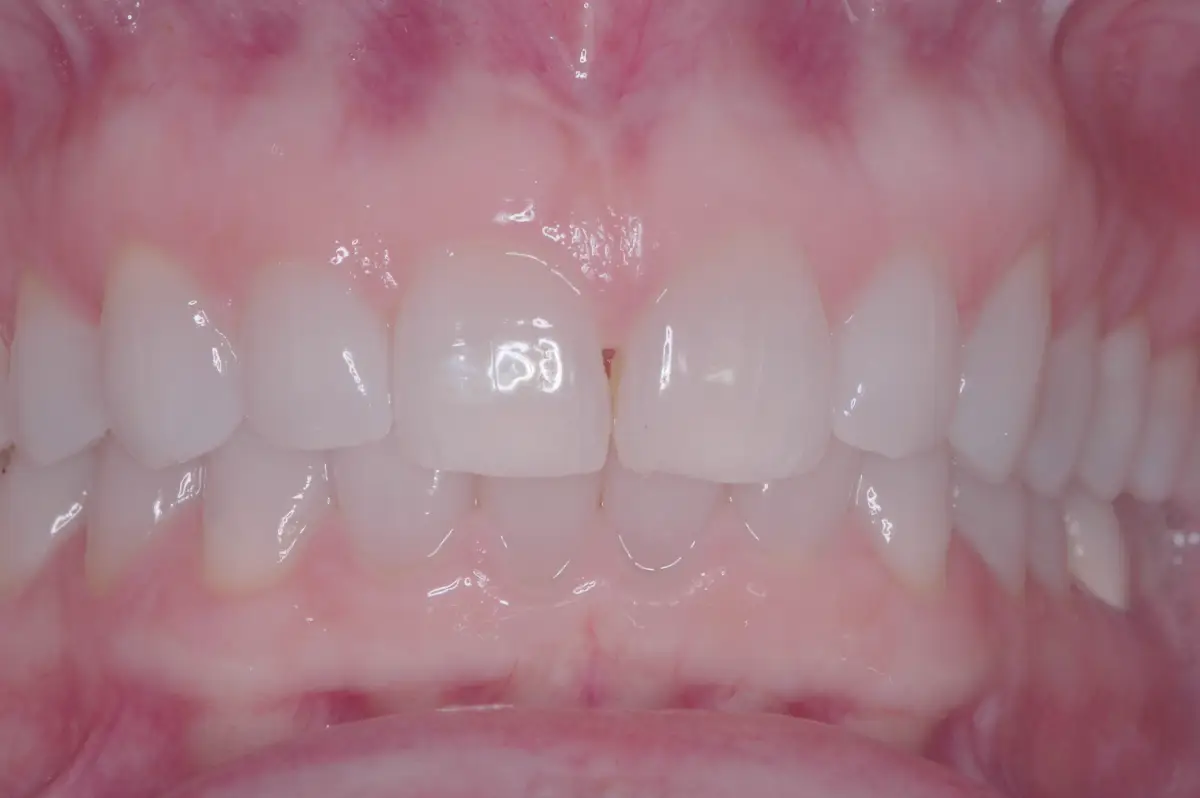

Frenectomy

before

after